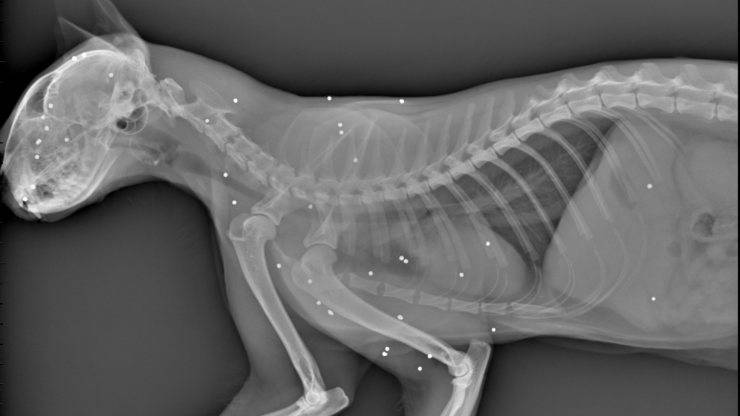

Un gatto si è trovato in serio pericolo di vita quando è stato trovato con 20 pallini conficcati nel corpo, il veterinario prova il tutto per tutto.

Una vicenda drammatica con protagonista un gatto ha avuto luogo nella giornata di lunedì 17 ottobre 2022 a Vittorio Veneto (TV). Il felino è stato trovato in condizioni al limite dell’immaginabile, infatti il suo corpicino contava bene 20 pallini al suo interno. Il piccolo ha rischiato seriamente di perdere la vita ma per fortuna è stato trovato in tempo e portato presso lo studio veterinario Sant’Andrea.

Trovato con 20 pallini al suo interno: gatto in condizioni critiche

Il veterinario che si è preso cura del gatto è Massimiliano Mele, il quale lo ha operato ed è riuscito a togliere tutti e venti i pallini incastrati in tutto il corpo. Le zone critiche, maggiormente colpite, erano la testa e le spalle. Un lavoro eseguito in maniera precisa in modo che il micio potesse avere un’altra possibilità di vita.

Nonostante il veterinario sia riuscito ad estrapolare tutti e venti i corpi estranei, non è riuscito a salvare uno dei suoi occhi, talmente tanto danneggiato che ha dovuto rimuoverlo per la sua sicurezza. “Si tratta dell’ennesima vicenda. Molto probabilmente lo hanno colpito da vicino e in più non casualmente, da come sono le ferite. Non è stato un colpo casuale esploso da un cacciatore. Il proprietario del gattino ha intenzione di sporgere denuncia”, ha raccontato il dottor Massimiliano Miele. Il nome del gattino è Polpetta ed era sparito da casa sua nella giornata di giovedì scorso.

Polpetta è un gattino di appena due anni e mezzo e il suo proprietario era in allerta già dalla settimana scorsa quando non è più tornato a casa. Il proprietario lo ha trovato domenica, inerme e pieno di larve di mosca e subito lo ha portato dal veterinario dove ha ricevuto tutte le cure di cui aveva bisogno. Secondo il veterinario del centro, l’intervento è riuscito ma non si esclude la possibilità di problemi neurologici dovuti alle lesioni causate dai pallini. Ha una lunga strada davanti a sé e ora non è più un pericolo di vita